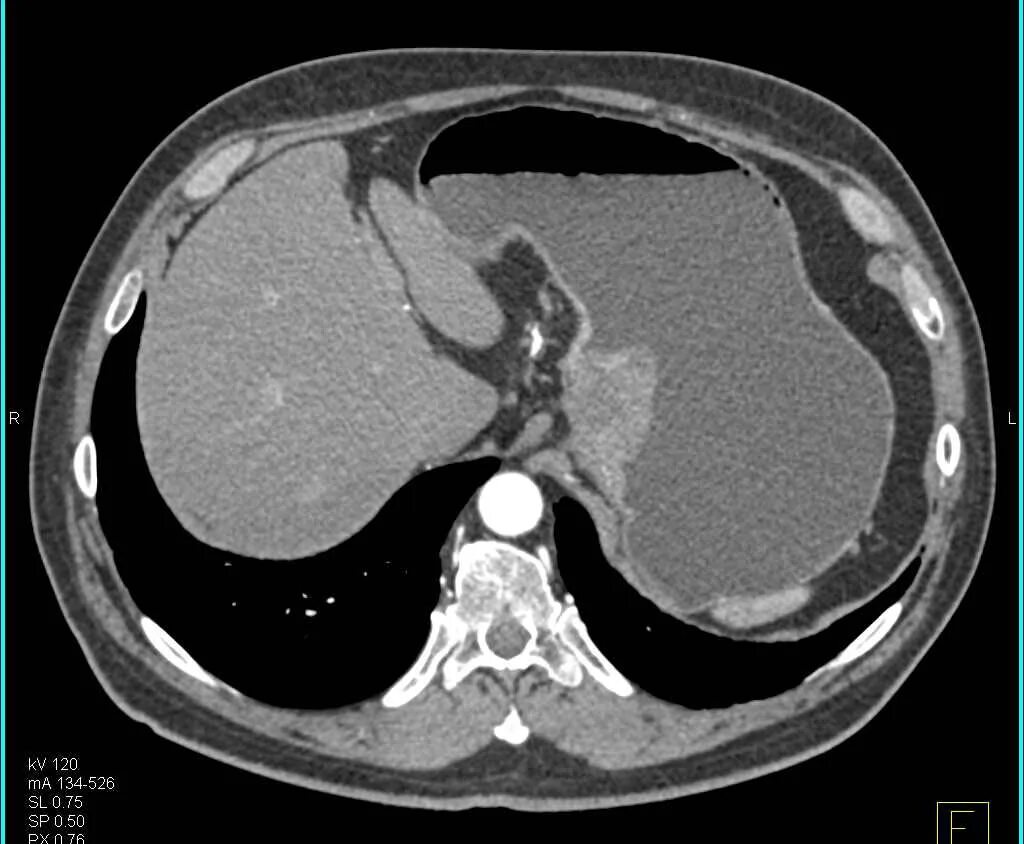

Язва желудка кт